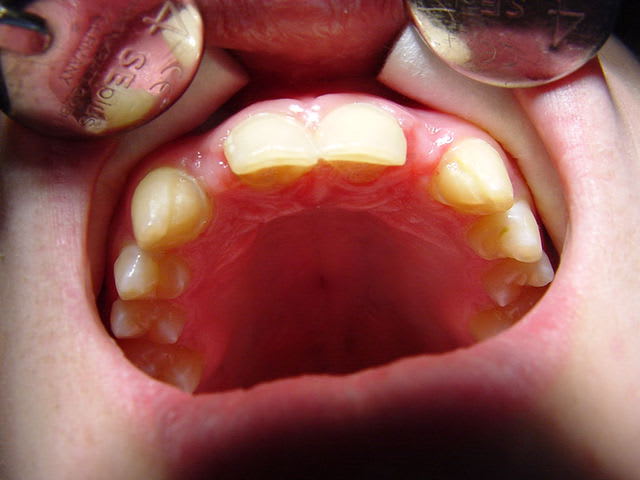

ceci par exemple

Dsc00090 mq4djg - Eugenol

Dsc00089 nurt6y - Eugenol